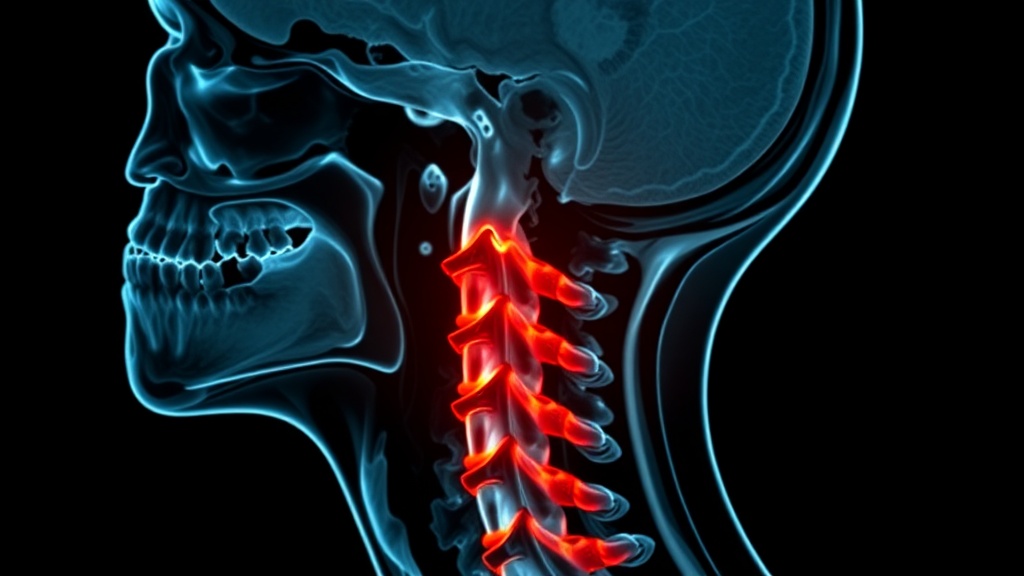

Katlyn Brooks, a 28-year-old mother from Michigan, endured two decades of debilitating symptoms before being diagnosed with hypermobile Ehlers-Danlos syndrome (hEDS). This genetic disorder compromised her body's connective tissue, leading to severe instability in her neck, where her skull was barely anchored to her spine. Doctors warned that her condition progressed to a point where any sudden movement could cause fatal internal decapitation, a rare and almost always lethal phenomenon.

Brooks faced years of being dismissed by medical professionals, with her symptoms of vomiting, dizziness, and fatigue attributed to anxiety or depression. This misdiagnosis delayed crucial treatment, exacerbating her condition to the point of gastroparesis, where her stomach stopped functioning properly, leading to severe malnourishment. Her severe craniocervical instability required a complex surgery to fuse her skull and upper vertebrae, a procedure difficult to find doctors willing to perform.